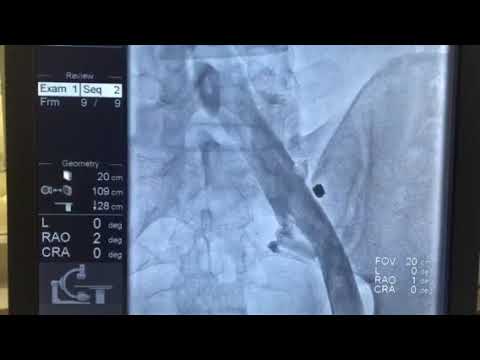

Флебография представляет собой важный диагностический метод, позволяющий визуализировать венозную систему. Эксперты отмечают, что процедура включает введение контрастного вещества в вену, что позволяет получить четкие изображения сосудов на рентгеновских снимках. Это исследование особенно полезно для выявления тромбозов, варикозного расширения вен и других заболеваний.

| Принцип метода | Введение контрастного вещества в вену с последующим выполнением серии рентгеновских снимков. | Контраст заполняет вены, делая их видимыми на рентгене. |

Для проведения флебографии вен нижних конечностей пациент направляется в рентгенологическое отделение. Перед тем как ввести контрастное вещество, пациента укладывают на специальный стол. Врач находит подходящую подкожную вену на голени или стопе, куда будет введен препарат. Это может быть сделано с помощью прокола вены (венепункция) или небольшого надреза под местной анестезией (венесекция). Затем через катетер вводится примерно 20 мл одного из препаратов, используемых в данной клинике, таких как омнипак, ультрависта и другие. Если требуется, на исследуемую конечность накладывается жгут, чтобы улучшить распределение контраста по венозной системе. После получения серии рентгеновских снимков жгут снимается, в вену вводится небольшое количество физраствора, и пациент ожидает результатов обследования.

Рентгеноконтрастная (классическая)

Наиболее распространенный метод исследования. Он осуществляется с применением стандартного рентгеновского оборудования. Пациента располагают на специальном столе, затем внутривенно вводят контрастное вещество, после чего выполняют серию рентгеновских снимков, фиксируя распространение контраста по венозной системе. При проведении венографии нижних конечностей на исследуемую ногу может быть наложен жгут, что способствует более эффективному распространению контрастного вещества.